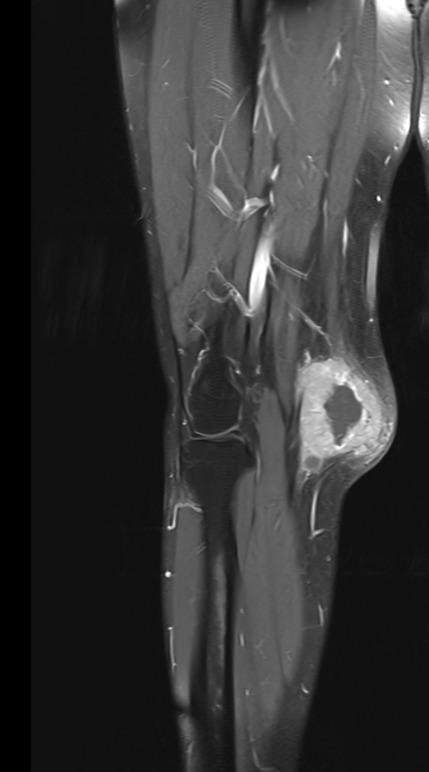

Muscle Cancer